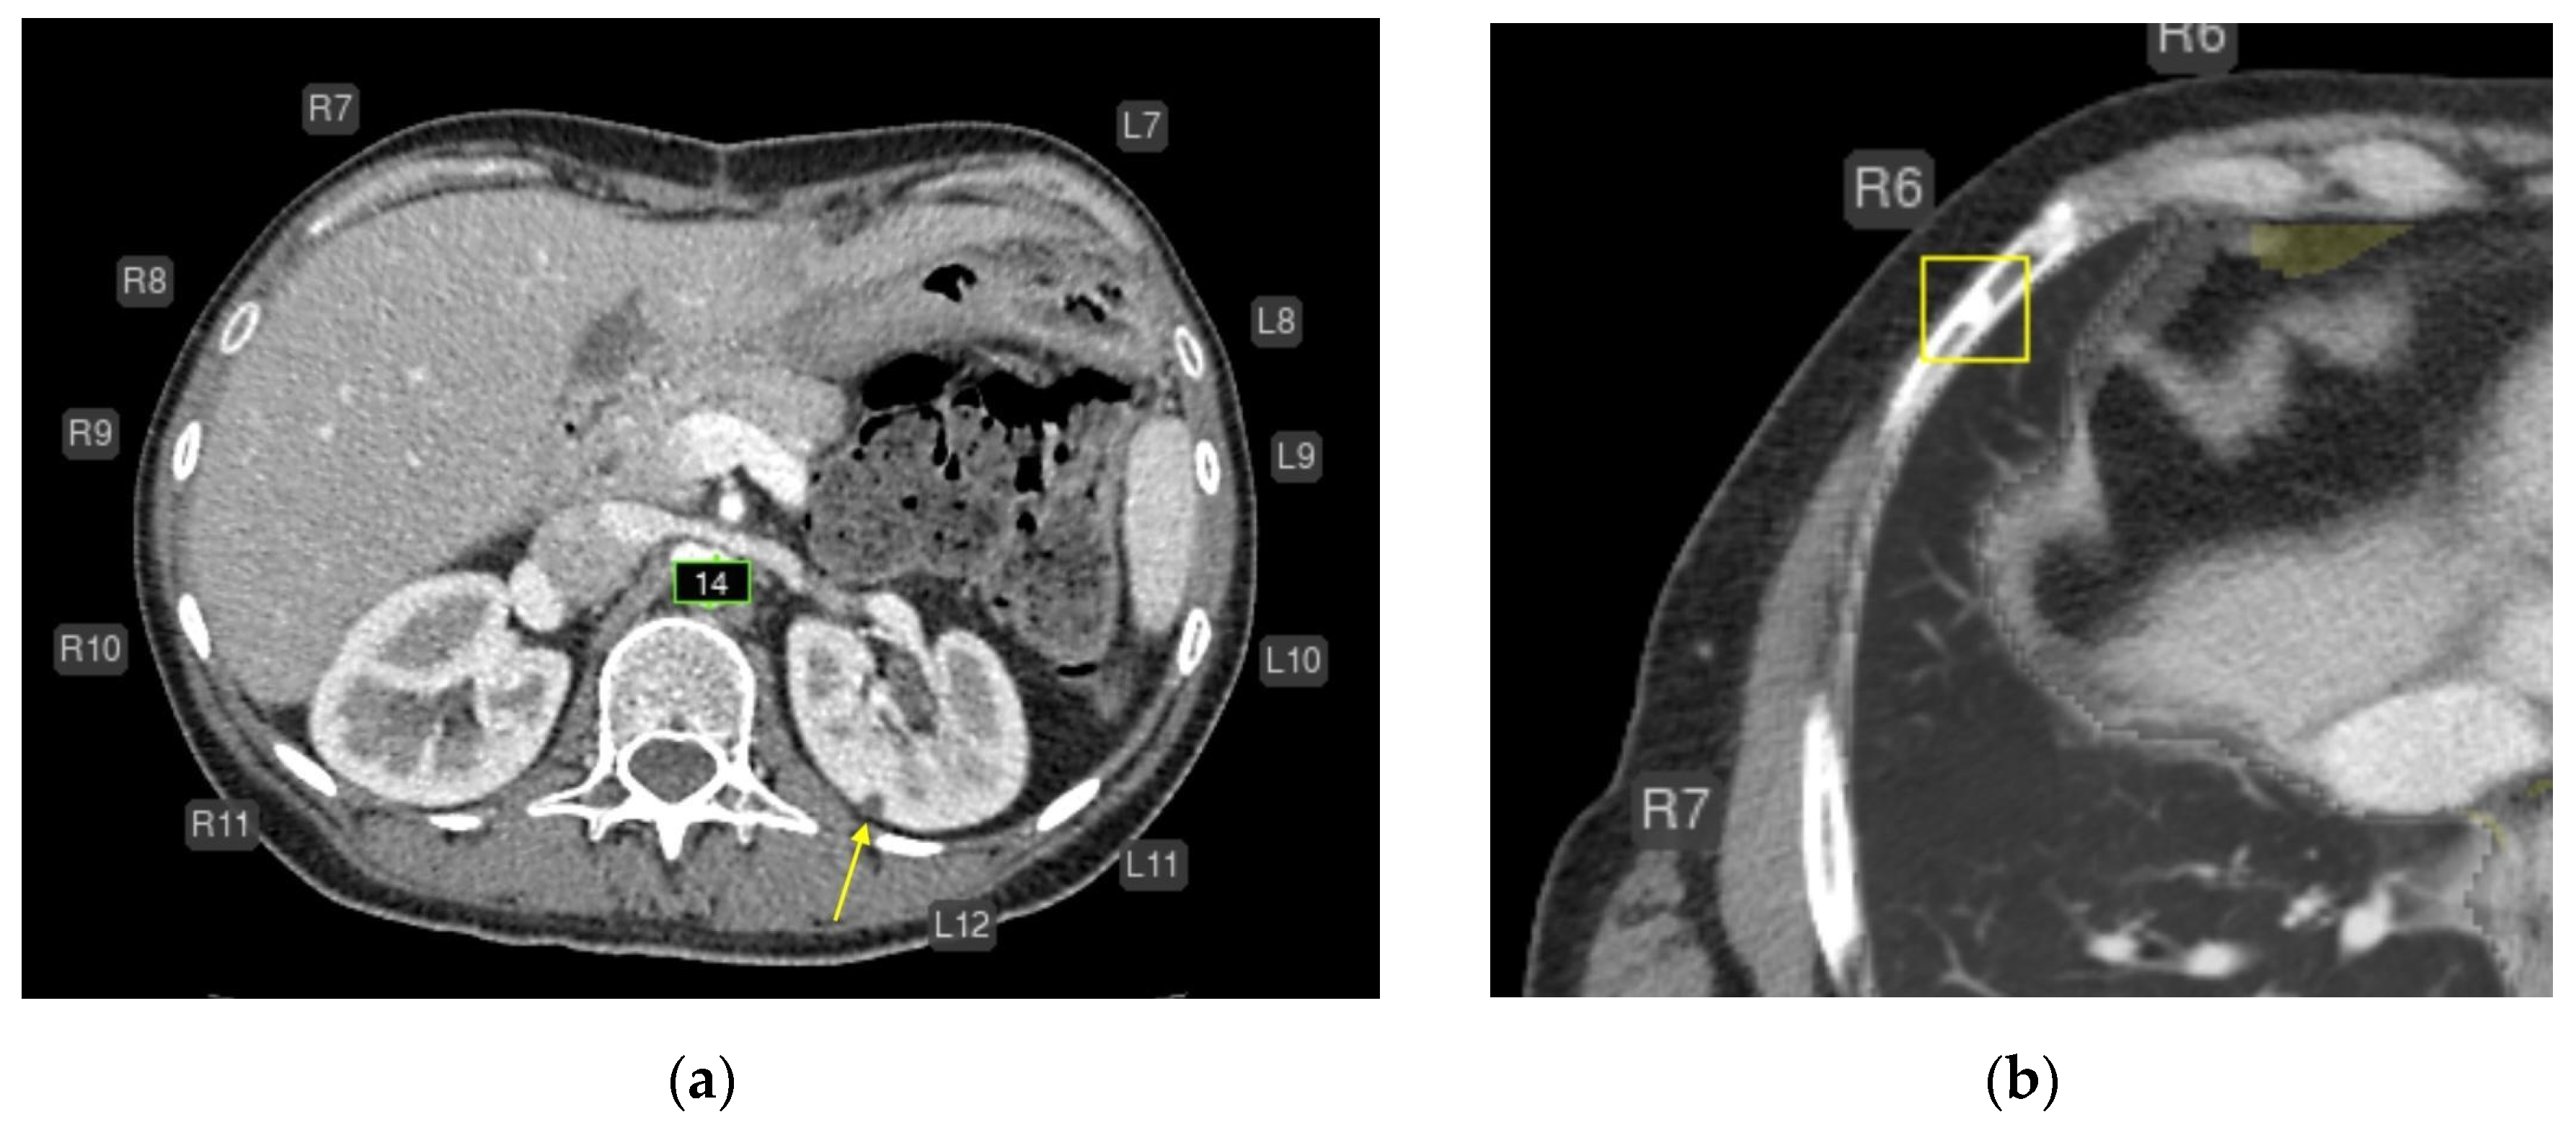

- Liver lesions (8);

- Renal lesions (2);

- Adrenal lesions (2);

- Impaired lung aeration (atelectasis, 2);

- Enlarged intrathoracic lymph nodes (3);

- Pulmonary nodule (1);

- Low vertebral body density (1);

- Urolithiasis (1) (Figure 4).